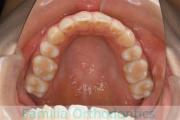

No.22V-029

- 叢生

- 上顎前突

- 19歳

- 男性

- 上:

- 8448

- 下:

- 主な使用装置:

- FEA 022

- 治療にかかった費用:

- 92万円

でこぼこを治したいということで来院されました。上下左右から親知らずも第一小臼歯も抜歯が必要で、歯科矯正アンカースクリューを併用して大臼歯を後ろに引っ張りながらの治療でした。3年弱、35回程度の通院が必要でした。

叢生が著しく、後戻りのリスクがあります。またアンカースクリューが必須のため、もしもスクリューが安定しないと、治療が難しく長くなってしまう恐れがありましたが、幸い脱落は見られませんでした。